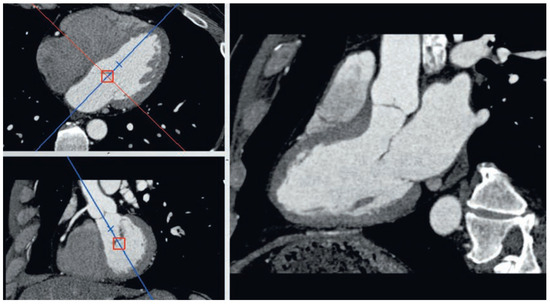

Coronary CT angiography (CTA) is emerging as a highly effective alternative imaging technique for the assessment of coronary artery disease (CAD). The rapid evolution of multidetector CT scanners has lead to major improvement in temporal resolution o...